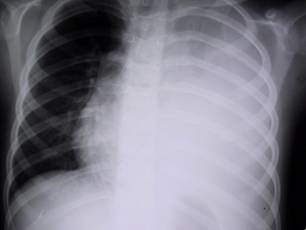

Рентген легких

Рентген грудной клетки является альтернативным, более качественным методом флюорографии. Поскольку у него большая разрешительная способность. Этот метод назначают при наличии подозрений на заболевания легких, тогда, как ФГ – для профилактики. К сведению, разница между флюорографией и рентгеном является в способности различия теней.

При помощи рентгена можно рассмотреть тени около 2 мм, а флюорографии – не меньше 5 мм. Функционирование R-графии основывается на попавшей в кадр выбранной области снимка в момент проникания через исследуемые ткани рентгеновского луча. В это время получается непродолжительная повышенная лучевая нагрузка, которая опасна развитием мутаций клеточного аппарата. Поэтому прежде чем направить на диагностику, врачом сравнивается получение пользы и вреда от процедуры.

Рентген назначают лишь в острой необходимости, при условии низкой величины от вреда исследования

Показания для проведения

Многие интересуются, чем отличается рентген от флюорографии. R-диагностика не относится к обязательной процедуре. Она назначается при наличии определенных показаний. Этот метод не используют в виде скрининга.

Показаниями для проведения рентгена является:

- пневмония;

- туберкулез;

- легочный абсцесс;

- отеки легких;

- плеврит;

- эмфизема;

- перелом ребра;

- онкология;

- гемоторакс.

Кроме того, данная диагностика показывает наличие инородного тела, уплотнений.